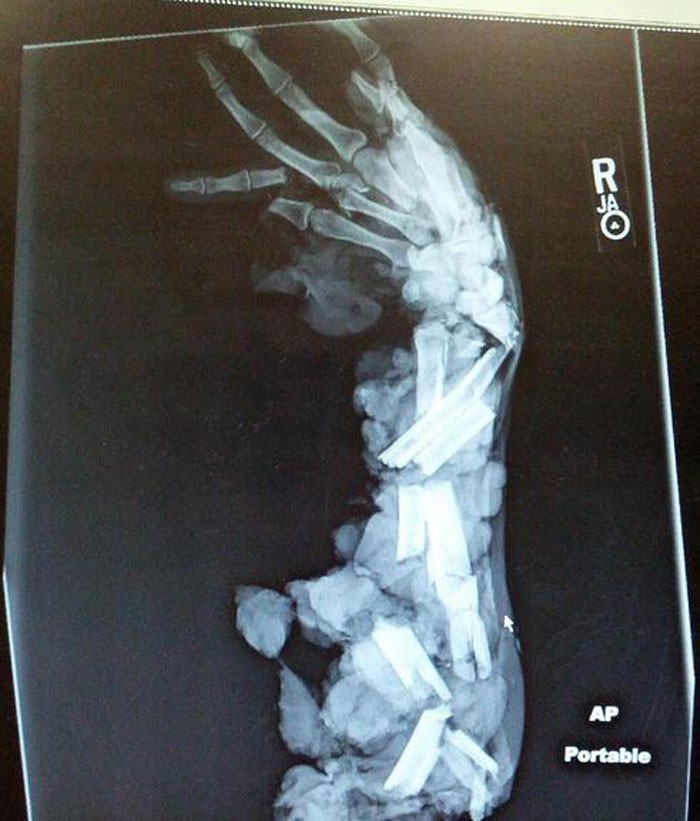

Jakarta - Deretan foto ini dibagikan netizen di media sosial, mulai dari Twitter hingga forum Reddit. Awas, siap-siap bergidik melihatnya.

Awas Foto Ini Bisa Bikin Bergidik